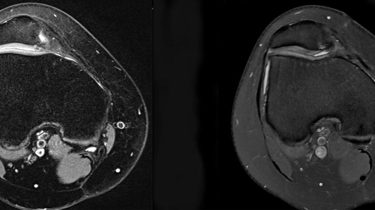

Hvilken type af operation, der skal vælges, afhænger af de biomekaniske forhold omkring knæet, og derfor skal du gennem både røntgen og MR-scanning.